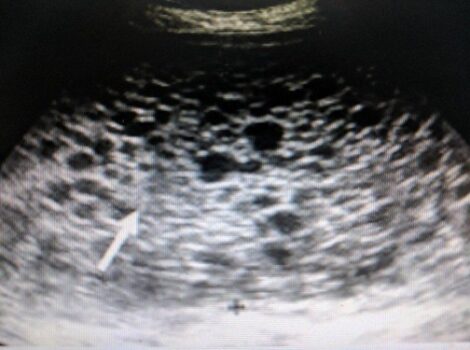

1. Định nghĩa Thai trứng là tình trạng lớp tế bào nuôi ở gai nhau phát...